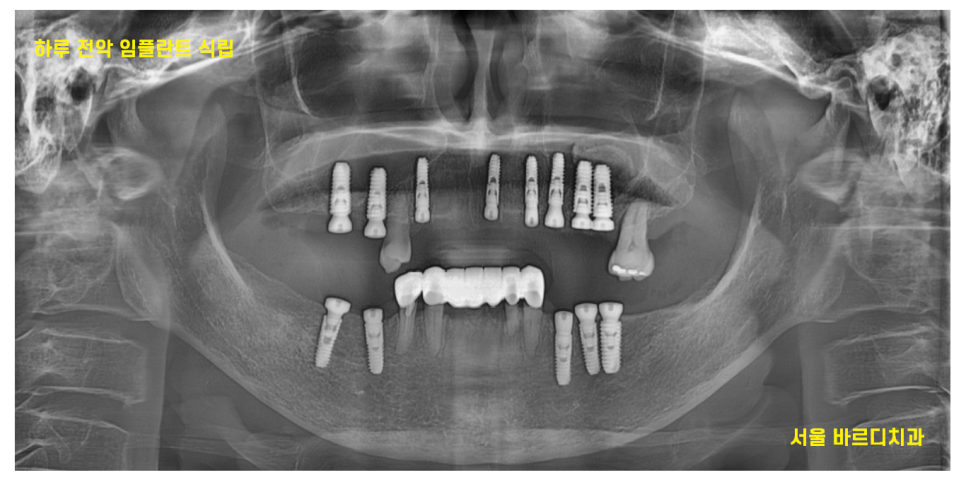

23.10.18

보험 임플란트 2개 사용이 가능해서

2개는 보험 임플란트로

나머지 11개까지 합해서

총 13개의 강동구 임플란트

하루에 다 식립해드렸습니다.

어금니 상실

앞니 빠진 부분 모두 모두요~

디지털 기술이 있었기에

하루만에 전체 임플란트가 가능했는데요~